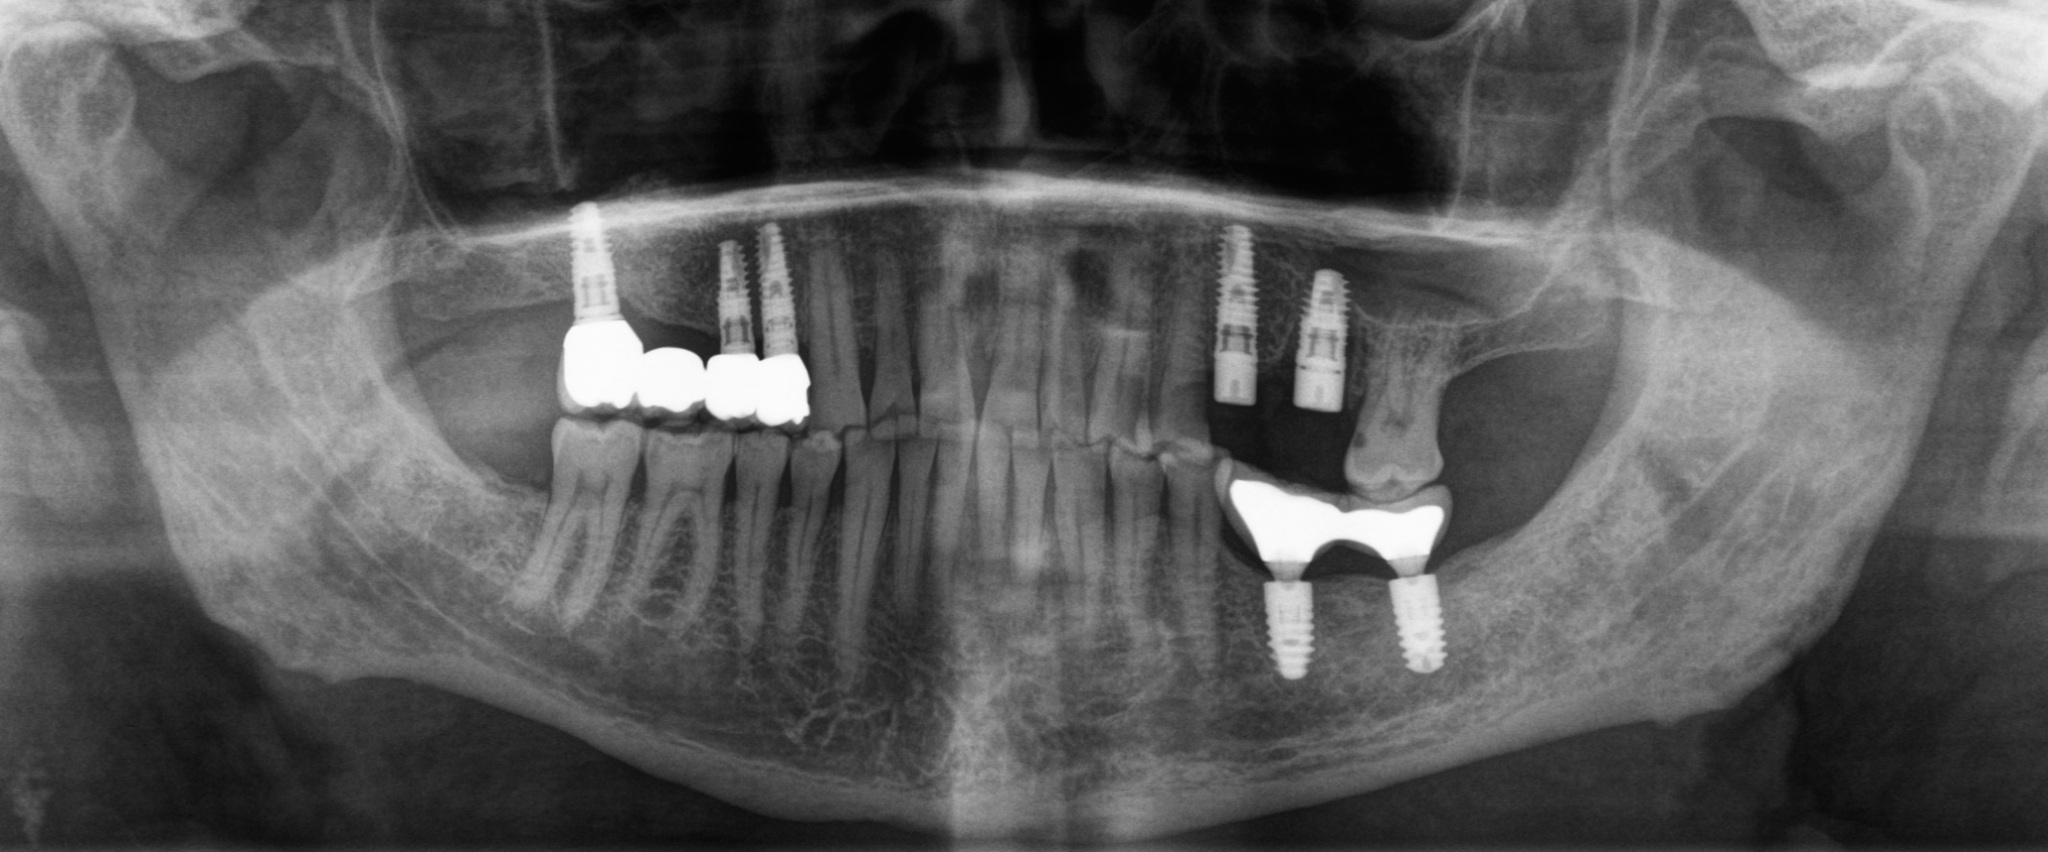

Первым контрольным рентгеновским снимком был этот:

На установленных ранее имплантатах в области 5 и 7 зубов на верхней челюсти справа (на снимке слева) стоял временный мостовидный протез. Пластик, из которого изготовляются временные конструкции не рентгеноконтрастен. Поэтому ничего кроме «белых полосок» в этой области вы не увидите. Средний срок службы подобных конструкций три месяца, но «по семейным обстоятельствам» пациент пользовался ими дольше обычного. Это привело к тому, что мостовидный протез треснул, аки старый трухлявый деревенский мост. В связи с этим, собственно, пациент и явился на прием. Напомню название статьи – «бруксизм». Сложно не заметить отсутствие зубов на противоположной стороне челюстей. Отсюда можно сделать логичный вывод, что основное (если не единственное) пережевывание пищи осуществлялось на стороне, где установлены имплантаты.

На снимке ниже перелом временной коронки:

Разницу в материалах можно видеть по белым полоскам в месте, где должна быть коронка. Если обычную временную коронку не видно, то при наличии металла на рентгеновском снимке его будет отчетливо видно.